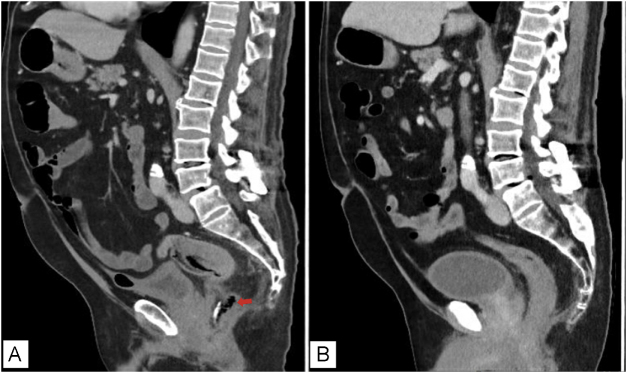

Case presentation: A 70-year-old male underwent a transrectal prostate biopsy which was complicated by the accidental injection of formaldehyde 4% into the rectum. One week later, he presented to our clinic with persistent rectal pain and was found to have an extensive rectal wall necrosis with perforation. Prompt intervention was undertaken with broad-spectrum intravenous antibiotics, transanal surgical debridement of necrotic tissue, and endoscopic vacuum therapy (EVT) to manage the rectal defect. The patient's condition improved with each sequential sponge change over an 11-day period, leading to cavity closure and granulation. He was discharged in stable condition on postoperative day 14. Two months later the rectal wound had completely healed.